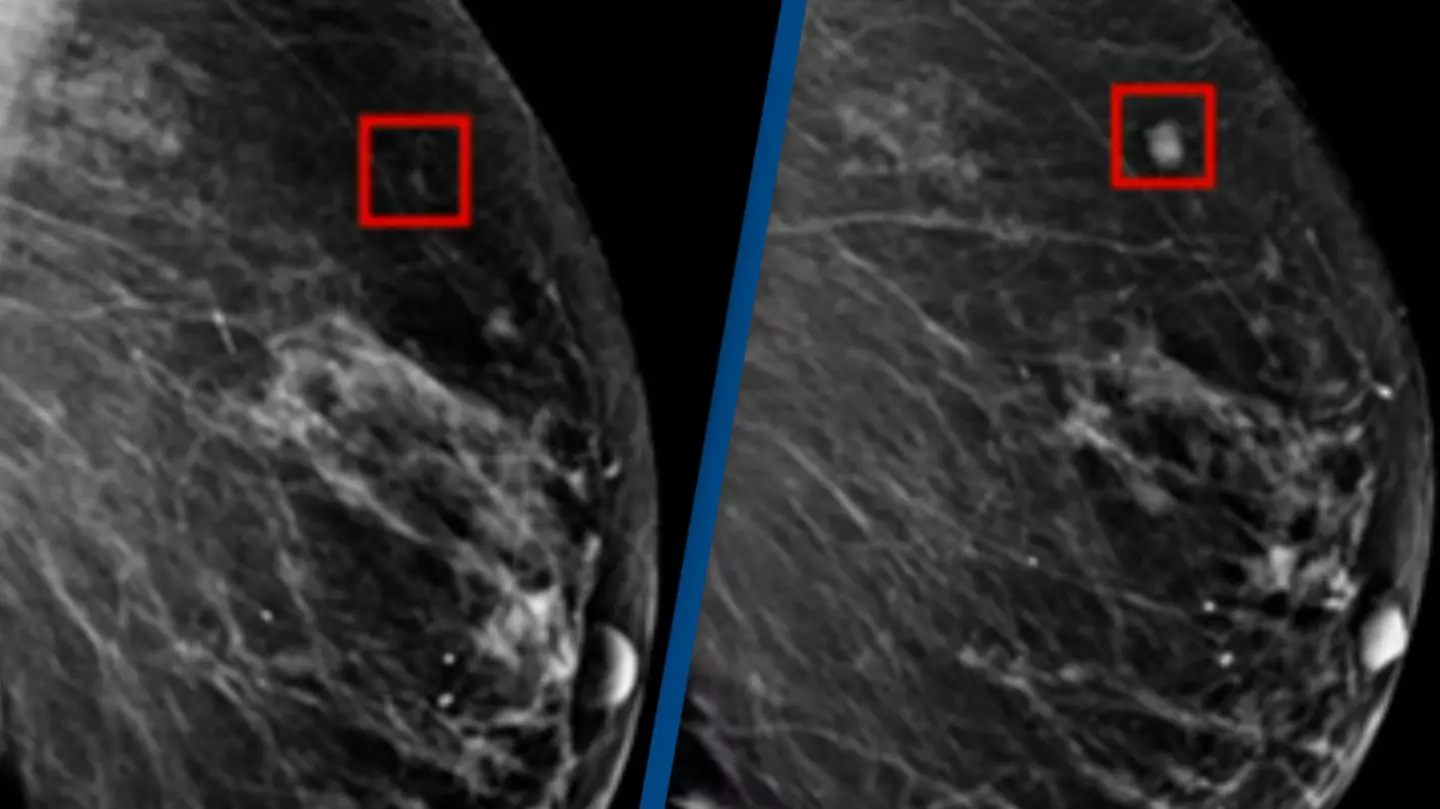

He said: "AI is a tool that machines use for looking at images and comparing those images to ones that have already been recorded in the machine to identify abnormalities.

"This technology can look at mammograms and identify areas that a human radiologist may want to look at more carefully.

According to the New York Times, the use of this AI technology in breast cancer screening has reduced the workload of a radiologist by around 30 percent while increasing cancer detection rates by 13 percent which sounds like entirely positive news.

They also report that the AI was tested with some of the most challenging cancer cases where the early signs of breast cancer had not been spotted by radiologists, with the AI successfully managing to identify the cancer.